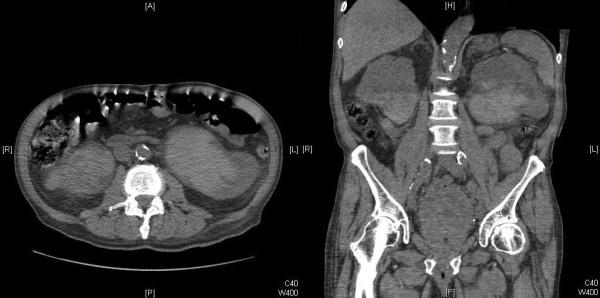

An 82-year-old Caucasian man was referred to our department with nocturnal enuresis and a palpable bladder. He was catheterized, produced a residual volume of 2900mL, and ended up becoming oliguric. Following investigations, he had bilateral nephrostomies. He was discharged 18 days after presentation.

一名82岁的白人男性因夜间遗尿和可触及膀胱被转诊至我科。对其进行导尿,残余尿量为2900mL,最终出现少尿。经过检查,他接受了双侧肾造瘘术。就诊18天后出院。